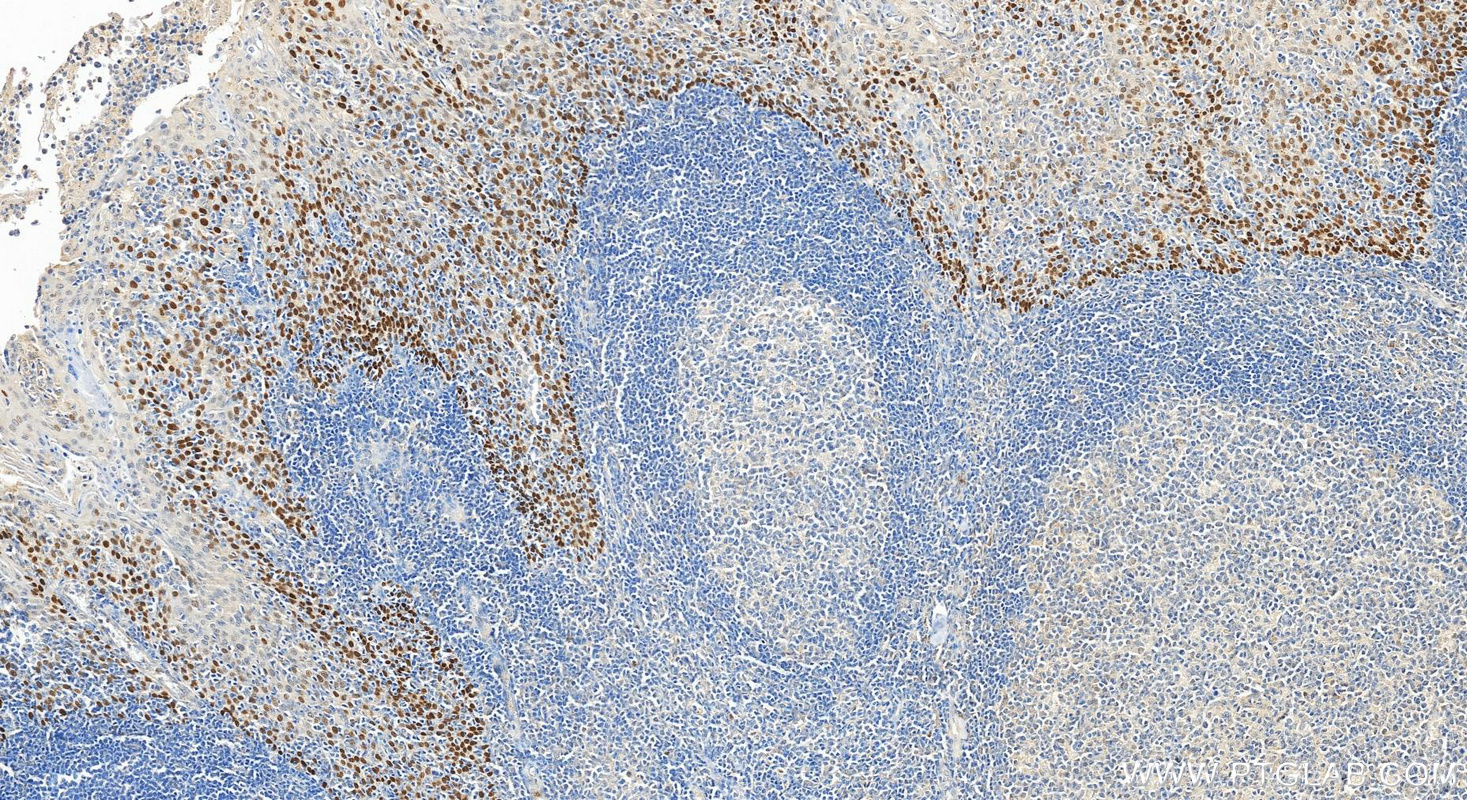

| Positive IHC detected in | human lung cancer tissue, human bowen disease tissue, human prostate cancer tissue, human tonsillitis tissue Note: suggested antigen retrieval with TE buffer pH 9.0; (*) Alternatively, antigen retrieval may be performed with citrate buffer pH 6.0 |

12143-1-AP targets p63 in WB, IHC, IF/ICC, IF-P, FC (Intra), IP, CoIP, ChIP, ELISA applications and shows reactivity with human, mouse, rat samples.

| 经测试应用 | WB, IHC, IF/ICC, IF-P, FC (Intra), IP, ELISA Application Description |

TP63, also named KET, P63, P73H, P73L and TP73L, belongs to the p53 family. It is a homologue of the tumor suppressor p53 and p73 genes. It is involved in malignancy acquisition and maintenance of cells. Unlike p53, the p63 gene encodes multiple isotypes with remarkably divergent abilities to transactivate p53 reporter genes and induce apoptosis. TP63 acts as a sequence specific DNA binding transcriptional activator or repressor. TP63 has 12 isoforms with MW 40kd(P40), 50kd(P60),63kd(P63) and 73kd(P73L).